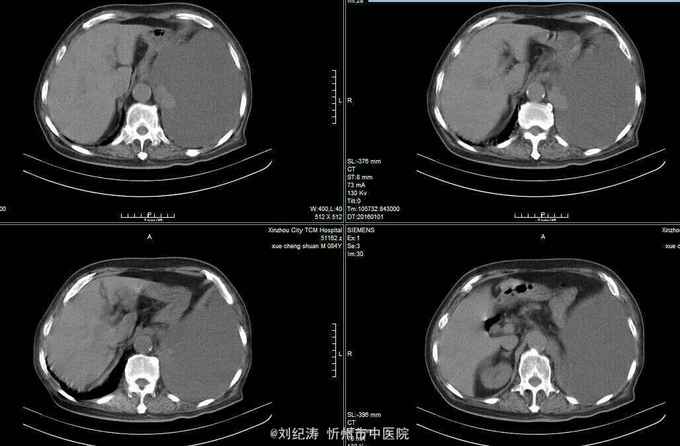

查体:ECOG评分:3分,生命指征平稳,浅表淋巴结未触及明显肿大,双眼睑无水肿,唇无发绀,颈软,双侧胸廓对称,左肺语颤增强,左肺呼吸音消失,右肺呼吸音粗,可闻及哮鸣音,心律齐,腹平软,肝脾肋下未触及,移动性浊音阴性,肠鸣音3次/分,双下肢无水肿。 辅助检查:血常规(2016.1.1):WBC:10.6*109/L,RBC:4.69*1012/L, PLT:165*109/L ,HGB:167g/L.生化(2016.1.1):谷丙转氨酶11U/L,谷草转氨酶11U/L,总蛋白60g/L,白蛋白33g/L,尿素:9.8mmol/L,肌酐:123umol/L,尿酸:251 umol/L,血糖:7.37 mmol/L;电解质:钾:4.79mmol/L,钠:123.5 mmol/L,氯:85.7 mmol/L,钙:2.03 mmol/L。肺部CT(2016.1.1):左肺完全萎缩,左侧胸腔大量积液,右肺未见异常,纵膈轻度右移,未见明显肿大淋巴结。

诊断: 1.左肺癌 左侧胸腔积液 左肺不张;2.2型糖尿病;3.低钠、低氯血症;4.低蛋白血症 治疗 完善检查,予以胸腔穿刺置管引流胸水以减轻心肺负荷,静脉给予抗感染、祛痰、止咳、平喘、提高免疫、扶正抑瘤、营养支持、调节电解质平衡及对症治疗。